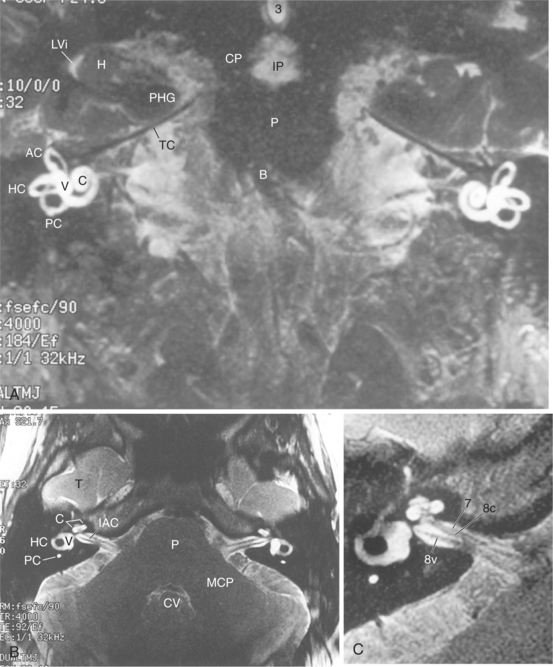

At its most peripheral level, the end organ of the vestibular system is primarily a mechanical system designed to identify movement of the head. It consists of a fluid-filled labyrinth and is bordered laterally by the middle ear and medially by the petrous portion of the temporal bone. The pathologic condition at this level is related to the structures involved. Figs. 38-1 and 38-2 show the mechanism of the vestibular system and the relationship of the vestibular system to the nearby structures of the brain and bony structures.

Figure 38-2 MRIs of the labyrinth. A, Coronal view. B, Axial view. C, Enlarged view. AC, Anterior semicircular canal; HC, horizontal canal; PC, posterior semicircular canal; C, cochlea; IAC, internal auditory canal; P, pons; 8v, eighth cranial nerve (vestibulocochlear nerve). (From Nolte J: The human brain: an introduction to its functional anatomy, ed 5, St Louis, 2002, Mosby.)